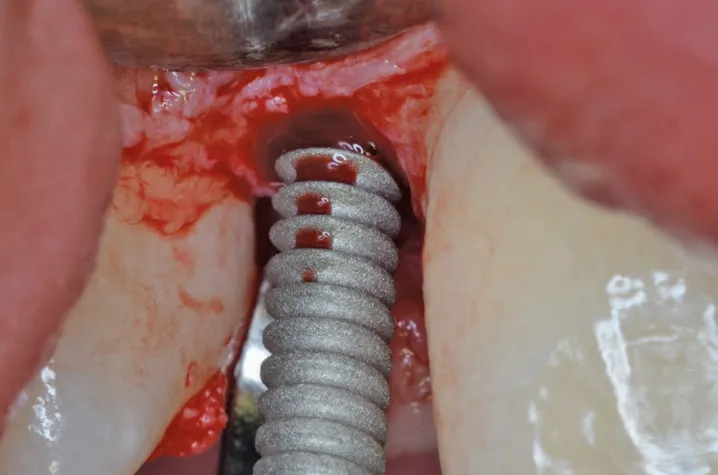

图 9 :植入 Axiom® 2.8 种植体。

图 10 :植入种植体。